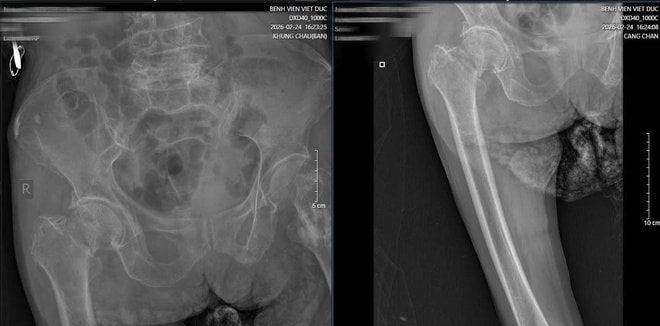

Cụ bà N.T.H (89 tuổi, Nghệ An) nhập viện trong tình trạng đau háng dữ dội, không thể đi lại sau khi ngã. Qua thăm khám tại BV Hữu nghị Việt Đức , các bác sĩ chẩn đoán cụ bị gãy cổ xương đùi.

Hình ảnh phim X-quang cụ bà 89 tuổi nhập viện gãy cổ xương đùi phải và hình ảnh chụp CT ổ bụng và phát hiện khối u ruột non gây lồng ruột.